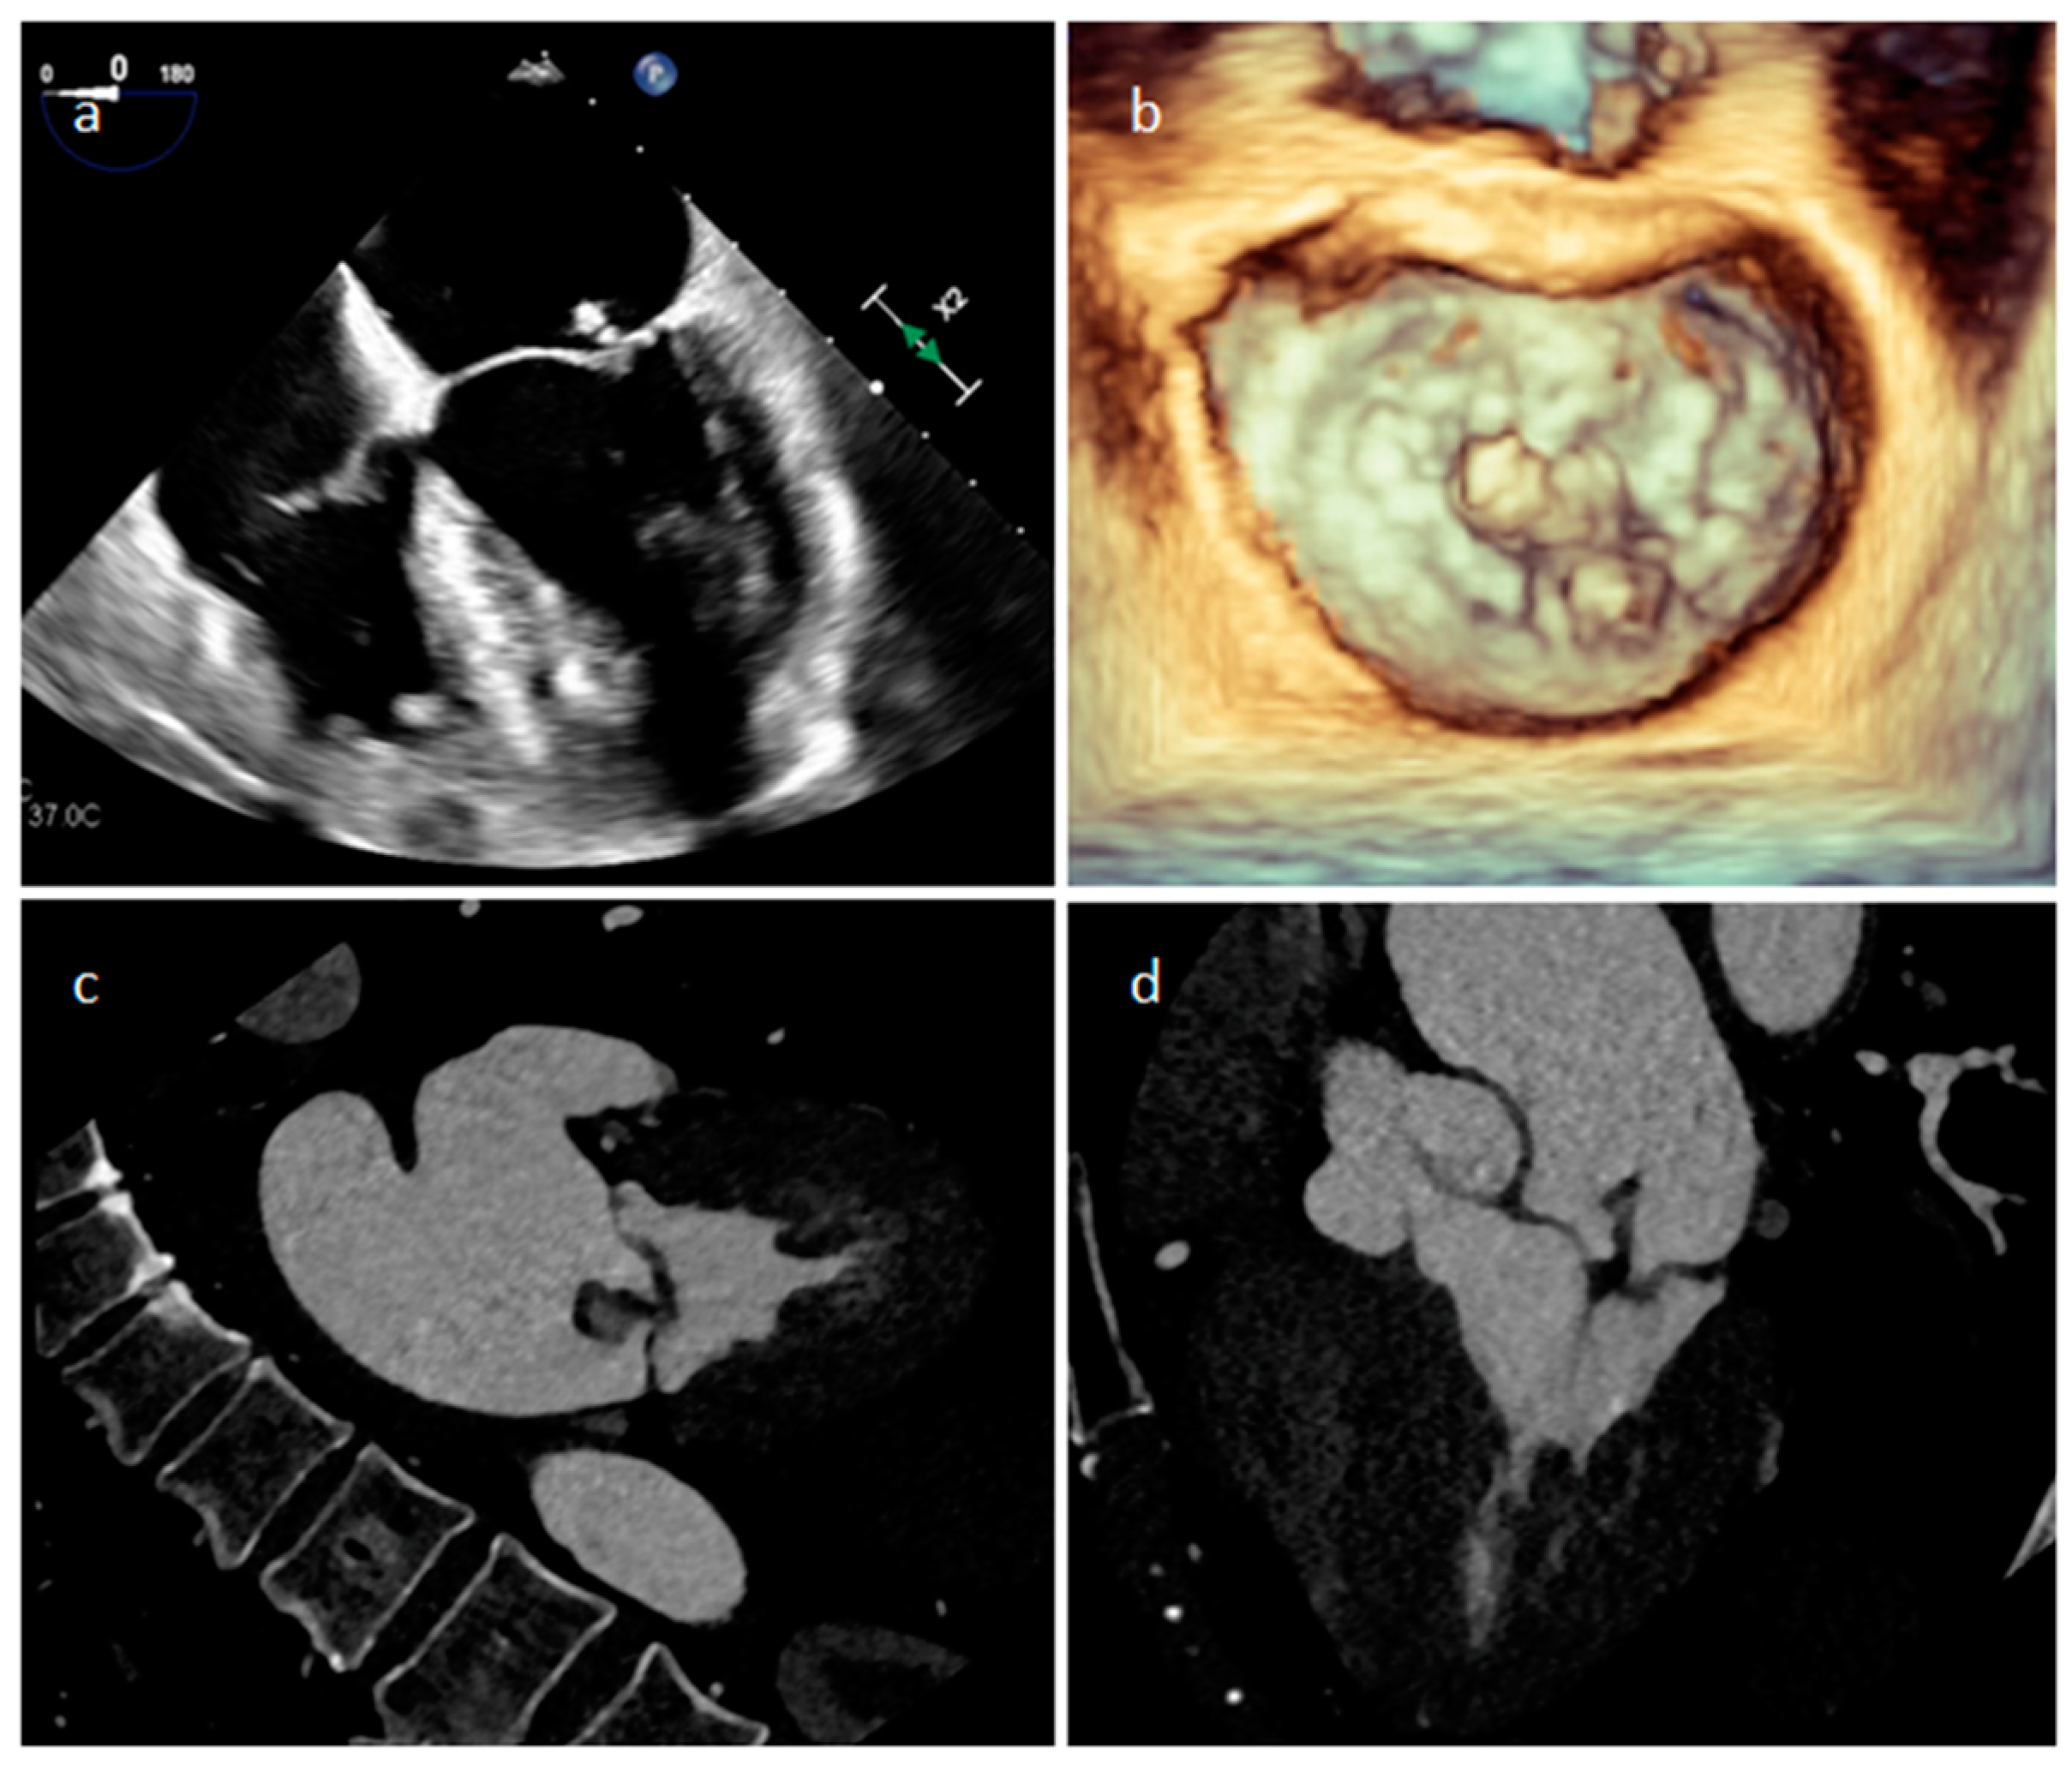

3.3. Mitral Annular Calcification and Its Caseous Degeneration

| Mitral annular calcification | Old patients | annular fibrous ring of the mitral valve | Asymptomatic | Calcifications, mitral valve | Hyperechoic | Calcific mass | Hypo T1w, hypo T2w, peripheral rim enhancement |

| Caseous degeneration of mitral annular calcification | Old patients | annular fibrous ring of the left atrio-ventricular valve | Asymptomatic | Calcifications, mitral valve | hyperechoic | Calcifications within and around the mass | Mildly hyper T1w, mildly hyper T2w, peripheral rim enhancement sometimes with central enhancement |